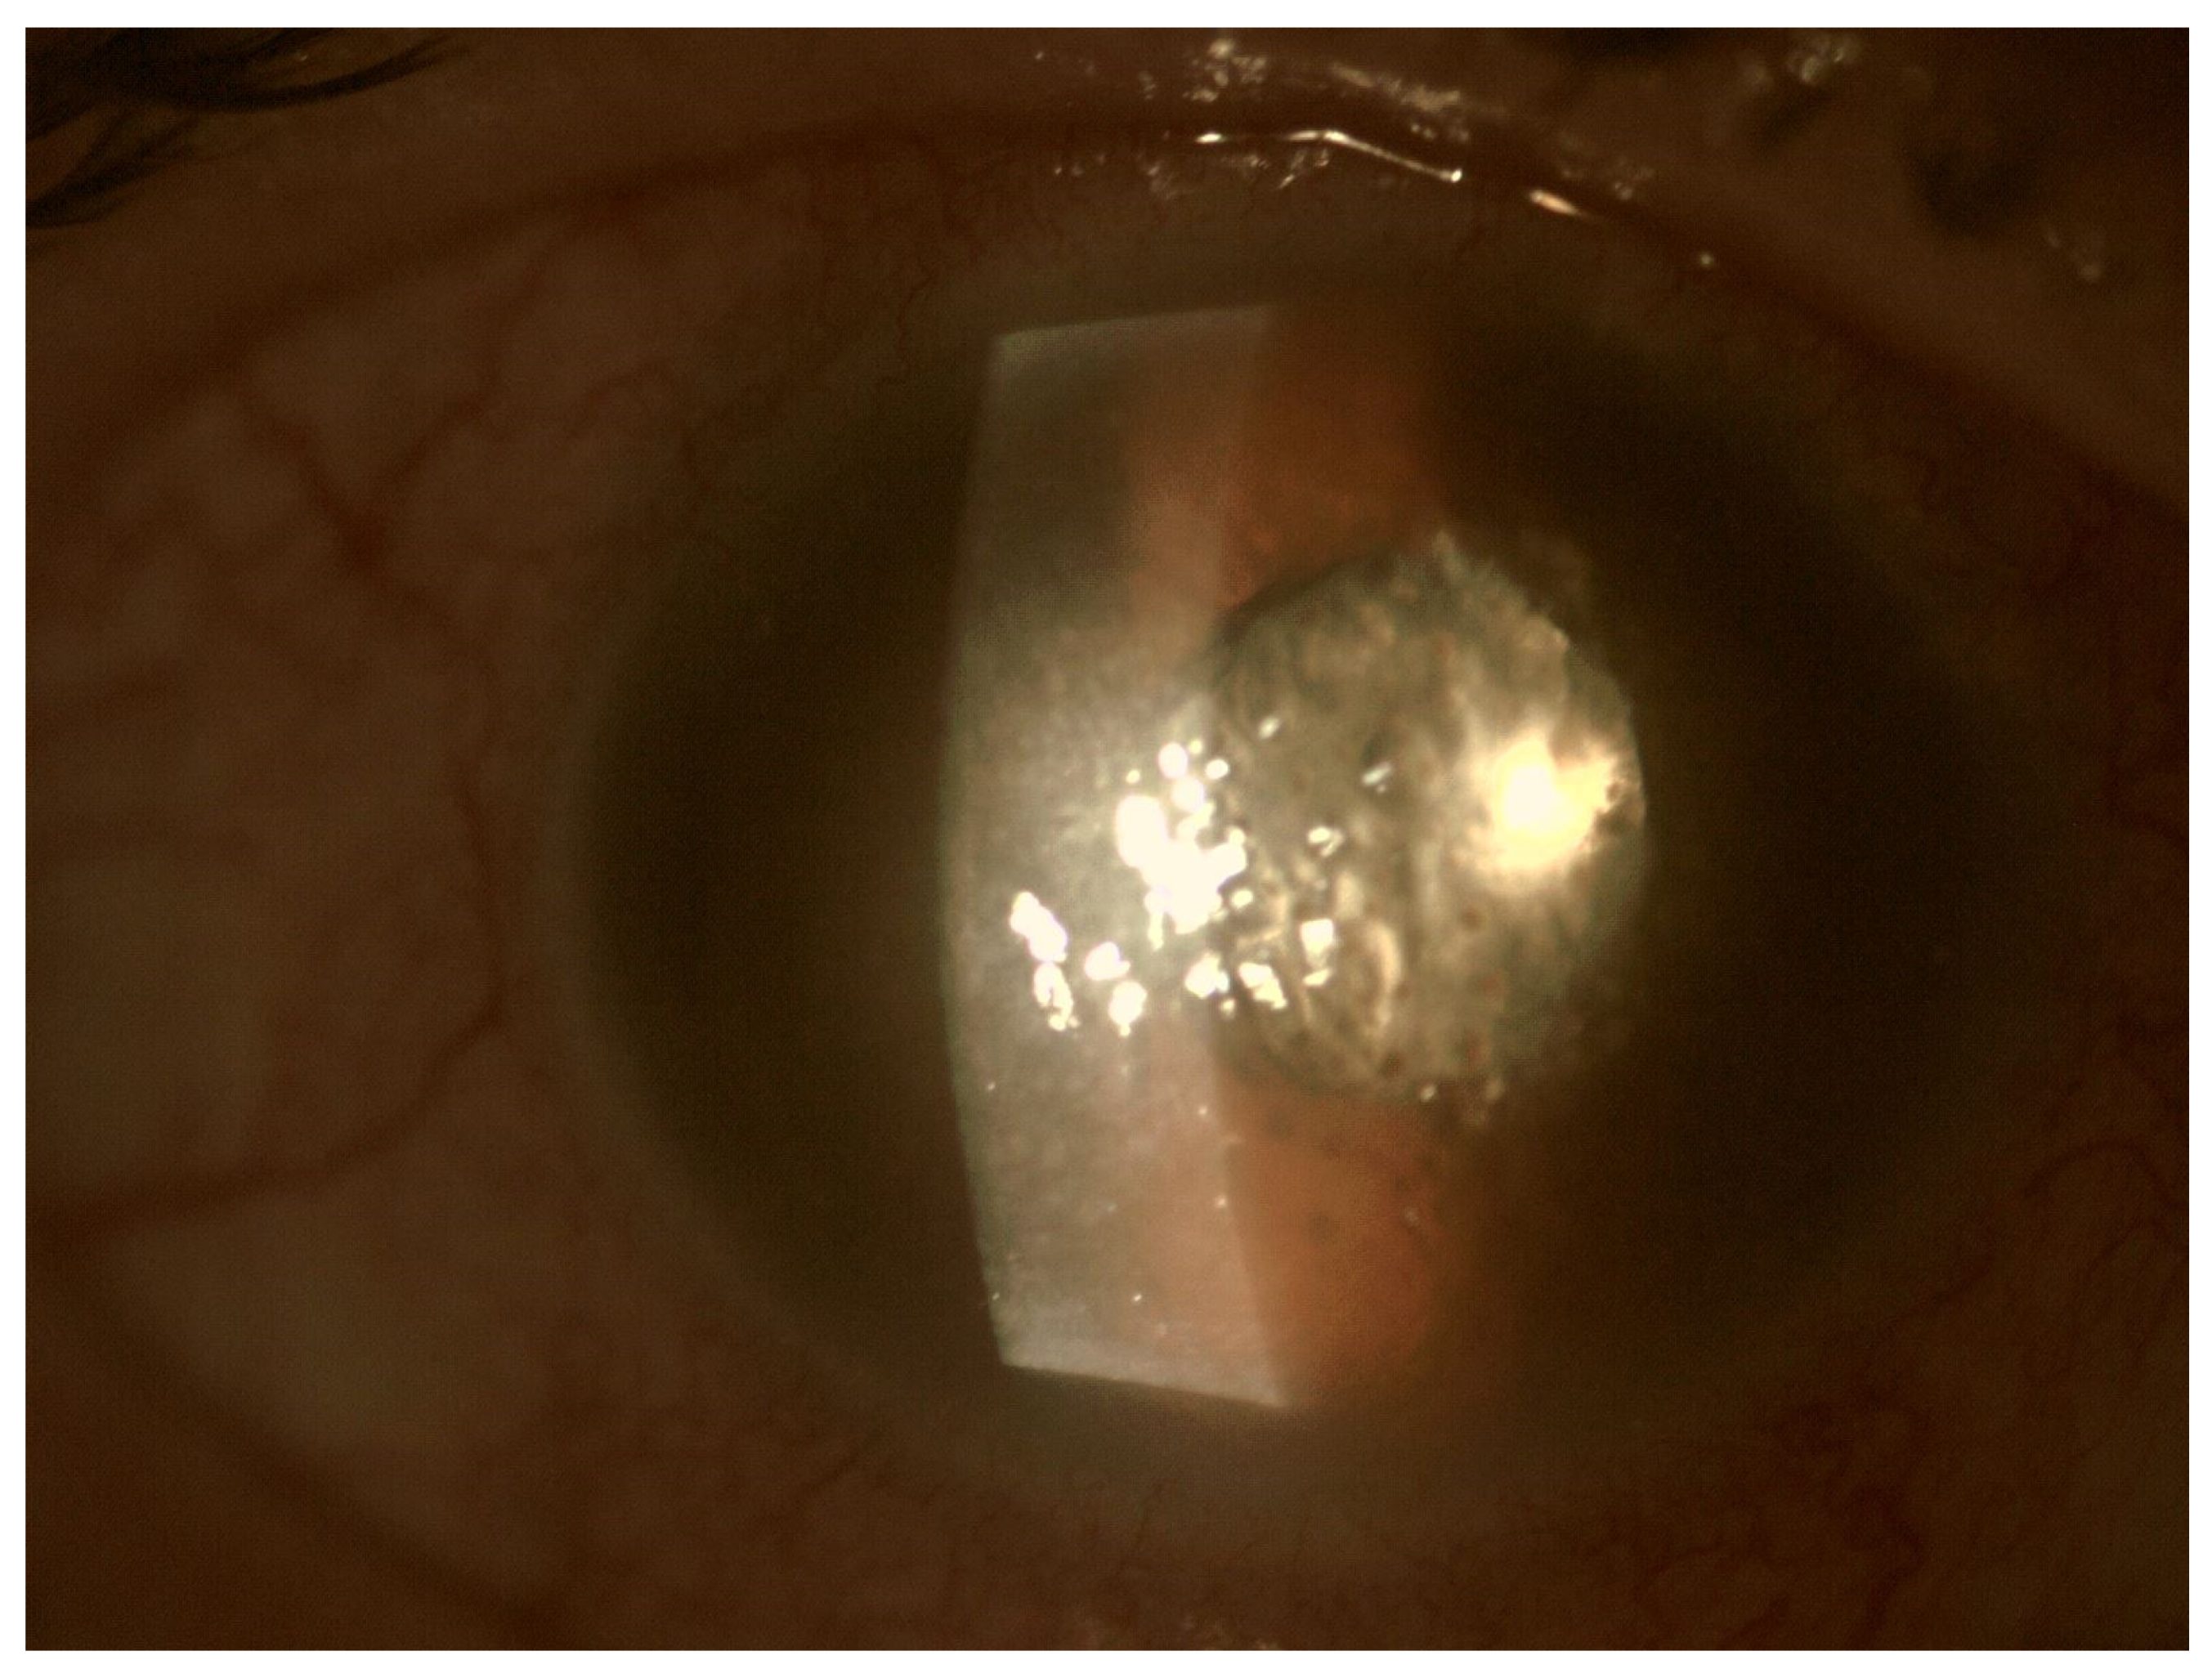

Figure 2.

Pre-operative photo of the anterior segment of the eye in the patient presented in Figure 1. Attention is drawn to the widening of the conjunctival blood vessels, damage to the corneal epithelium and cell deposits on the endothelium. Due to the poor transparency of optical centers, the view into the fundus was significantly impaired.

In EE, the transparency of optical media is often reduced. The cornea opacification and Descemet’s membrane folding are common. Tyndall can be found in the aqueous humor, often there is also hypopyon in the anterior chamber (Figure 3 and Figure 4). Inflammation and bacterial toxins are responsible for cataracts development and leakage of the lens proteins into the anterior chamber. In the case of posterior synechiae, the pupil does not respond to mydriatics (Figure 5).